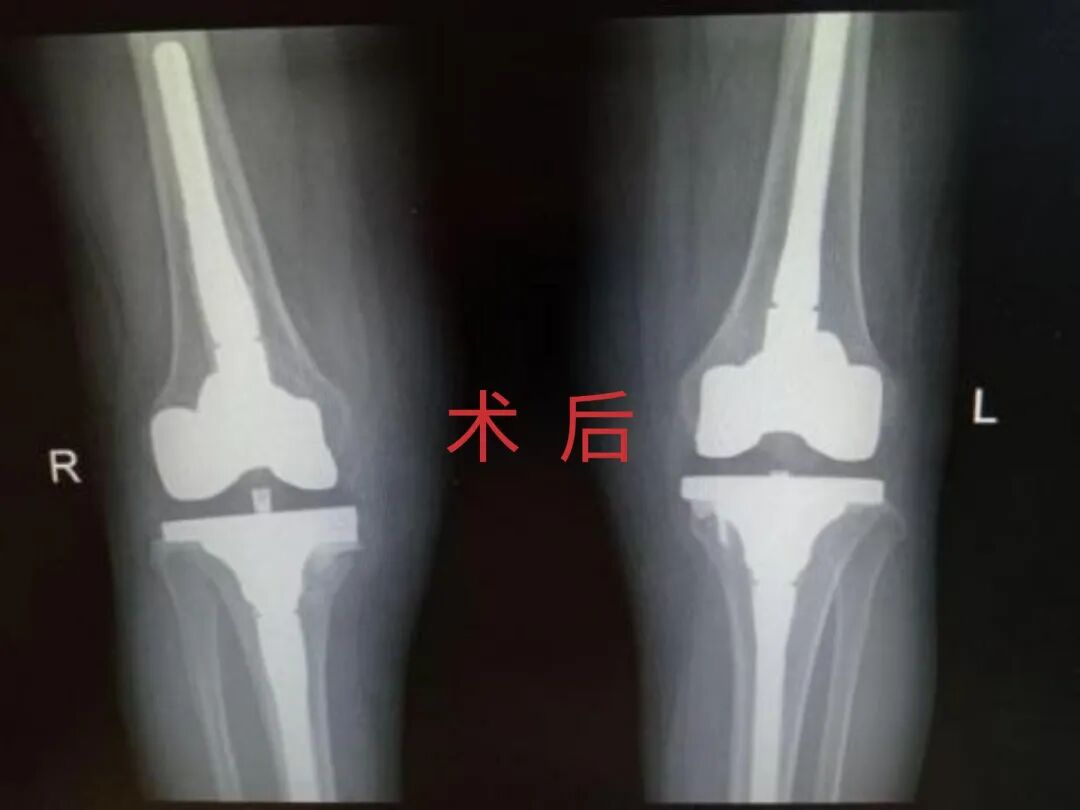

4月23日,贵州航天医院第58次晨读会由我院骨科副主任医师张艳金作学术交流,他以“加速康复指导下的快速手术”为题,详细讲解了老年股骨粗隆间骨折与儿童四肢骨折的临床诊疗难点,结合加速康复外科(ERAS)核心理念,重点阐述了ERAS理念在两大人群中的创新实践,实现患者入院后6至24小时内即可接受手术治疗。针对老年髋部骨折患者,提出通过多学科协作(MDT)与微创手术优化围术期管理,在确保安全前提下缩短术前等待时间,实施精准化麻醉及术后康复方案,可有效降低并发症发生率、改善患者生活质量和预后效果。在儿童骨折领域,强调微创术式与心理干预并行的双轨策略,既减少手术创伤对骨骼发育的影响,同时关注患儿心理疏导,实现生理功能与心理健康同步康复。并通过典型案例的影像学资料与随访数据,直观展示了ERAS理念指导下骨科治疗模式的创新成果。 贵州航天医院骨科 专家简介 赵学平 中共党员,骨科党支部书记、主任,主任医师 临床擅长:从事骨科临床工作30余年,对骨科常见疾病的诊治具有丰富的临床经验。 世界中医药联合会脊柱康复专业委员会常务理事,中华中医药学会整脊分会常务委员,中国中西医结合学会骨伤科分会肢体矫形功能重建与康复专家委员会常务委员,中国研究性医院学会骨科创新与转换专业委员会关节外科学组保髋工作委员会常委,中国康复技术转化及发展促进会骨外科与康复技术转化专业委员会常务委员,泛珠三角区域运动医学联盟(PPRD-SMA)理事会常务理事,中国研究型医院学会运动医学专业委员会委员,贵州省中医药学会整脊分会副主任委员,贵州省中西医结合学会银质针专业委员会副主任委员,贵州省康复医学会骨与关节专业委员会常务委员,贵州省人民医院骨科专科联盟常务理事,贵州省康复医学会骨内科专业委员会常务委员,中华医学会贵州省骨科学会委员,贵州省康复医学会脊柱脊髓专业委员会常务委员,贵州省运动医学分会委员,贵州省康复医学会骨与软组织肿瘤专业委员会委员,遵义市医学会创伤分会副主任委员,贵州省康复医学会骨内科专业委员会遵义地区分会常务委员,遵义市医疗事故鉴定、伤残鉴定、工伤鉴定、司法鉴定专家。 长期从事骨科临床研究及教学工作,在国家级、省部级杂志发表论文20余篇,SCI论文2篇,参与主编骨科专著2部,主持省部级科研项目2项,参与指导省部级、市级科研项目6项。 陈明勇 骨科副主任,副主任医师 临床擅长:从事创伤骨科工作约20年,对骨缺损、骨不连、骨肿瘤、肢体畸形等的肢体矫形重建及功能重建,慢性化脓性骨髓炎的根治治疗、糖尿病足的保肢治疗、快速康复理念(ERAS)下的老年骨折的诊治,四肢复杂骨折的诊治,四肢骨折等微创手术治疗具有丰富的临床经验。 2004年毕业于遵义医学院临床专业,曾在中国人民解放军总医院、广西医科大学第一附属医院、上海第六人民医院骨科进修。中国中西医结合学会骨伤科专业委员会横向骨搬移治疗糖尿病足及微血管网再生学组首届委员,遵义市医学会创伤分会常务委员。 瞿 辉 中共党员,骨科副主任医师 临床擅长:对骨科的常见病、关节外科、脊柱外科及运动医学疾病的诊治具有丰富的临床经验,熟练掌握骨科手术操作技术。 毕业于遵义医学院临床医学系,2005年前往广州中山大学第一附院骨显微医学部进修学习,2011年前往成都华西医院进修学习,并多次在省内外学习骨科相关知识,是中华医学会骨科分会会员。 赵兴东 骨科主任医师 临床擅长:擅长骨科的常见病及各种创伤、四肢骨折创伤修复、骨感染、手足疾病的诊治和手足体表畸形的矫形整复,熟练掌握骨科四肢骨病及创伤的手术操作技术,尤其在四肢关节复杂性损伤、手足外伤、组织缺损创面、难治创面的皮瓣修复方面及平足、高弓足矫形方面及四肢慢性疼痛诊治、康复方面具有丰富的临床经验。 硕士研究生,毕业于遵义医学院临床外科系,2015年前往山东省立医院手足外科进修学习;遵义市医学分会创伤分会第一、二届委员,遵义市手外科医学会第二委届员会常务委员;在省级及省级以上期刊发表文章9篇,参编著作2部,参与主持并完成市级课题1项,参与市级课题2项、省级课题1项。 张艳金 中共党员,骨科副主任医师 临床擅长:从事骨外科工作16年,对复合伤、多发伤的救治、四肢骨干骨折、关节周围骨折、骨肿瘤、骨髓炎等诊治具有丰富的临床经验。 中共党员,硕士研究生,2006年本科毕业于山西医科大学第二临床医学院,2011年研究生毕业于北京军区总医院;在“老年COPD患者合并髋部骨折的诊治”国际合作课题组研究两年,在老年髋部骨折的诊治方面具有丰富的经验,并发表论文6篇;主持遵义市级课题1项,承担遵义医科大学的临床教学工作,获得遵义医科大学优秀带教老师荣誉。编撰有《骨科疾病诊疗精粹》一书,开展2项新技术,编撰地方规范《务川自治县创伤骨科常见疾病诊疗规范》一书。 张俊凯 骨科副主任医师 临床擅长:从事骨科临床工作28年,对创伤骨折、骨感染、骨缺损、骨不连等外科诊治,四肢骨折的微创手术治疗,四肢复杂骨折(如关节内粉碎性骨折、多发骨折等)的损伤控制及手术治疗等具有丰富的临床经验。 1995年毕业于遵义医学院临床专业,2009年前往复旦大学附属医院骨科进修1年。 卢懿明 中共党员,骨科副主任医师 临床擅长:从事骨科工作18年,对创伤骨折、四肢骨折的微创手术治疗、四肢复杂骨折(如关节内粉碎性骨折、多发骨折等)的损伤控制及手术治疗,尤其是髋部骨折的PFNA等微创技术,踝关节骨折、膝关节周围骨折的Mipo微创技术等具有丰富的临床经验,开展了4项新技术,发明6项新型专利技术。 2005年毕业于遵义医学院临床专业,2017年,前往南方医科大学第三附属医院骨科进修半年,回院后运用Mipo技术对骨干骨折及干骺端骨折的治疗技术,同时积极开展骨盆骨折、髋臼骨折腹直肌外侧切口的应用;发表了多篇专业论文,经常参与省内外学术交流会授课,获得医院荣誉称号多个。 邬夏荣 骨科副主任医师 临床擅长:从事骨科工作16年,对四肢复杂骨折、骨肿瘤的诊治,尤其是足踝创伤、慢性踝关节损伤、平足症等诊疗具有丰富的临床经验。 2006年毕业于遵义医科大学临床医学专业,曾在陆军军医大学西南医院进修学习,发表多篇骨科学术论文。 余德怀 中共党员,骨科副主任医师 临床擅长:从事骨科工作10余年,对运动医学、骨关节、脊柱外科常见病、多发病的诊治具有丰富的临床经验。 硕士研究生,2011年毕业于遵义医学院临床医学专业,曾前往遵义医科大学附属医院运动医学专业进修学习;是贵州省医学会运动医学分会青年委员,西部关节镜联盟委员;发表多篇骨科学术论文。 冯 乾 骨科副主任医师 临床擅长:从事骨科工作近20年,熟练掌握骨科多发病及常见病的诊治,尤其对脊柱退变性疾病的诊断及治疗具有丰富的临床经验,主要研究脊柱微创相关治疗方式,能熟练开展椎间孔镜及UBE。 曾前往北京大学第三医院进修学习疼痛及椎间孔镜、首都医科大学友谊医院专业进修脊柱内镜;是贵州省康复医学会第三届脊柱脊髓专业委员会委员;发明专利3项、发表脊柱外科专业论文多篇。 赵小锋 中共党员,骨科副主任医师 临床擅长:从事骨科临床工作11年,对骨科常见病、多发病诊疗有较为丰富的临床经验,擅长脊柱相关疾病诊断及治疗,尤其是颈、腰、腿疼痛疾病诊断及治疗,擅长胸腰椎骨折微创经皮穿刺内固定术、经皮穿刺椎体成形术、经皮穿刺脊柱内镜下腰椎间盘摘除术、单纯开创腰椎间盘摘除术、腰椎滑脱复位椎间植骨椎融合内固定术、腰椎管狭窄减压融合内固定术及人工髋、膝关节置换术等。 2012年毕业于遵义医学院外科学专业硕士研究生,2019年参加“遵义市115医学人才精英计划”于上海交通大学第一附属医院培训学习,2023年于北京大学第三人民医院脊柱外科进修学习,曾获得遵义市优秀医师荣誉称号。 遵义市手外科第一届委员,遵义市医学会创伤分会第一届委员,遵义市医学会创伤分会第二届委员,贵州省康复医学会第三届脊柱脊髓专业会委员,遵义市医学会烧伤与整形外科学分会委员,发表论文5篇,其中国家级核心期刊1篇,SCI论文1篇,主持市级课题1项并结题,参与市级课题2项。 贵州航天医院骨科 简介 基本情况 贵州航天医院骨科组建于20世纪60年代,前身是以创伤和断肢(断指)再植闻名于世的上海市第六人民医院骨科,中国断肢(断指)再植的奠基者、中科院院士陈仲伟等著名专家、学者多次莅临科室指导医疗、教学,是贵州省最早拥有专业骨科技术科室之一,在70年代开展了贵州省首例断肢(断指)再植手术。组建50余年来,诊治患者已逾百万,挽救了无数的伤病员,成为了保障遵义地区人民群众健康的重要支撑。 经过几代人的不懈努力,今天的骨科,已由创伤骨科发展至骨病、骨肿瘤、骨结核等领域,现有脊柱外科、关节外科、四肢创伤、手足外科四个亚专科,成为了集医疗、教学、科研于一体的综合学科,是贵州省临床重点专科、遵义市临床重点专科、遵义市骨科临床医学中心、遵义市基层骨科专科联盟理事长单位。 科室目前开放床位110张,共有医护人员50余人,副高级以上专家18人,硕士研究生15人。拥有一流骨科医疗设备多台,每年不定期选派优秀技术骨干到全国各大知名医学院校进修、学习、参观、交流,并邀请国内、国外知名专家教授来院进行交流、指导,通过不断引进国内外先进的诊疗技术,科室医疗技术水平稳步提升,为广大人民群众提供了优质的医疗服务。 专科特色 骨一科 (一)骨缺损、骨不连的肢体与功能重建 胫骨横向骨搬移技术治疗糖尿病足: (二)慢性骨髓炎的根治治疗 (三)肢体缺血性疾病如糖尿病足、脉管炎的保肢治疗 (四)皮瓣修复 (五)复杂创伤的治疗 (六)老年髋部骨折及小儿骨折快速手术 老年髋部骨折: 骨二科 (一)胸腰椎骨折微创经皮椎弓根螺钉固定术 (二)老年性骨质疏松性患者腰椎滑脱脊柱内固定术(骨水泥螺钉) (三)V形双通道脊柱内镜技术(VBE)腰椎融合术治疗腰椎退行性疾病 (四)老年性骨质疏松性骨折(PVP/PKP)术 (五)人工髋关节置换术 (六)双侧股骨头坏死人工全髋关节置换 (七)右侧全髋置换术后假体周围骨折翻修 (八)人工膝关节置换术 (九)人工膝关节假体松动翻修 (十)关节镜技术 传统手术切口 关节镜技术切口 诊疗范围 骨一科 1.四肢创伤、矫形。 2.手、足踝外科。 骨二科 end